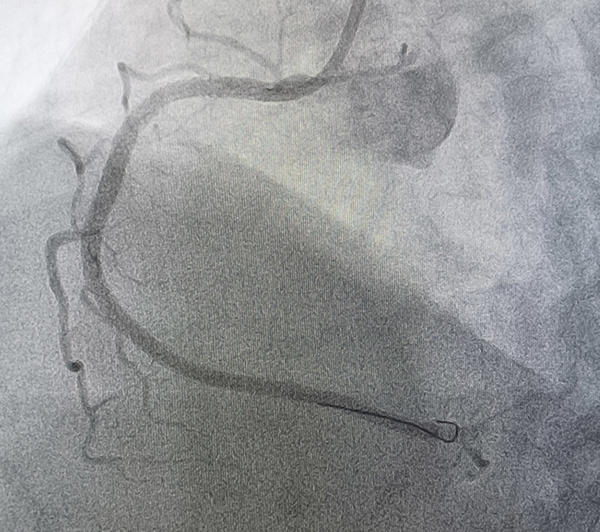

After that, the RCA was engaged with a JR4 6Fr guide catheter and advanced distally a 0.014” Runthrough floppy guidewire, then the occlusion site was predilated from distal to proximal with 2.0x15mm balloon and advanced 3.0x48mm everolimus stent from proximal segment and was deployed at 14 atm, however significant lesions were observed in the distal segment, so we decided to advance a 2.5x48mm everolimus stent and was deployed in distal segment at 13 atm and splice a third 2.75x24mm everolimus stent at 13 atm with TIMI3 final flow (“Full metal jacket”) (Figure 5,6) (Video 1).

Figure 6: "Full metal jacket" in RCA with TIMI3 final flow